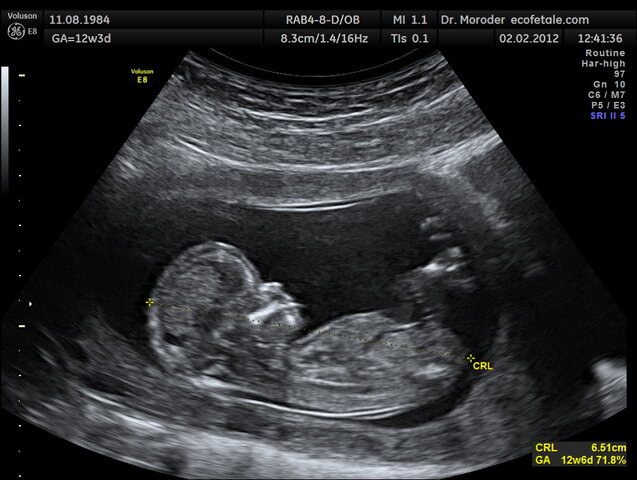

Au cours du grossesse, le cerveau du fétus se développent en commençant avec le télencéphale, le diencéphale, le mésencéphale, le métencéphale et le myélencéphale, les cinq majeur parties du cerveau. Ceci ce prend place approximativement au cours du septième semaine du grossesse! Après que les majeurs components du cerveau se développent, le bébé commence à connecter les milliards de nuerons avec les stimulations qu'il expériences dans le ventre, comme les bruits et les voix d'extérieure.